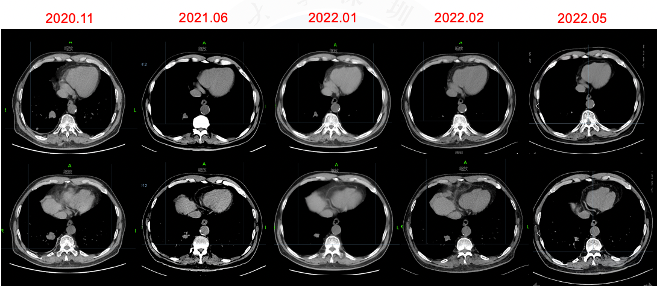

图5胸部CT

√ 2021.06.28胸部CT:右肺下叶后基底段肿块约21×23×21mm大小,右肺下叶后基底段(Img230)见结节影,大小为7×7mm,较前缩小。疗效评价PR。

图11胸部CT

方案:2022.02 阿美替尼110mg qd 口服。

2022.05.06 胸部CT:右肺下叶后基底段肿块约13×17×18mm大小,较前(22.02)明显缩小,疗效评价PR,未再发生间质性肺炎。

图12胸部CT